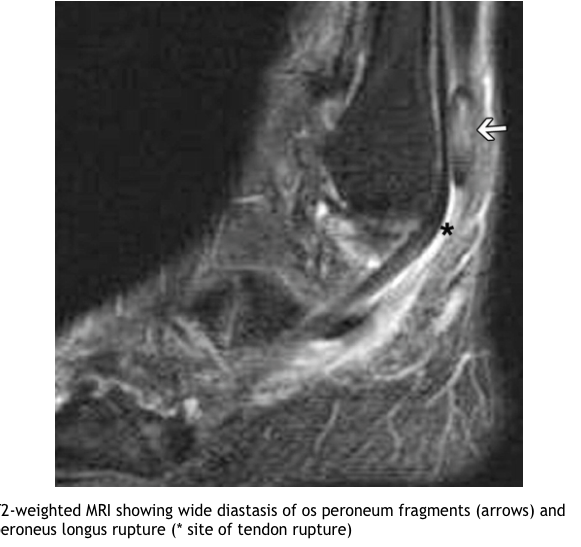

Describe the pathophysiology of injury/fracture?

What investigations are useful in DDx of Os peroneum?